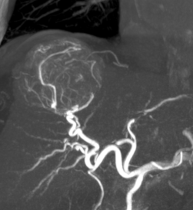

- Indications and follow-up of radiology treatments for portal hypertension and portal vein thrombosis

- Role of interventional imaging in abdominal trauma